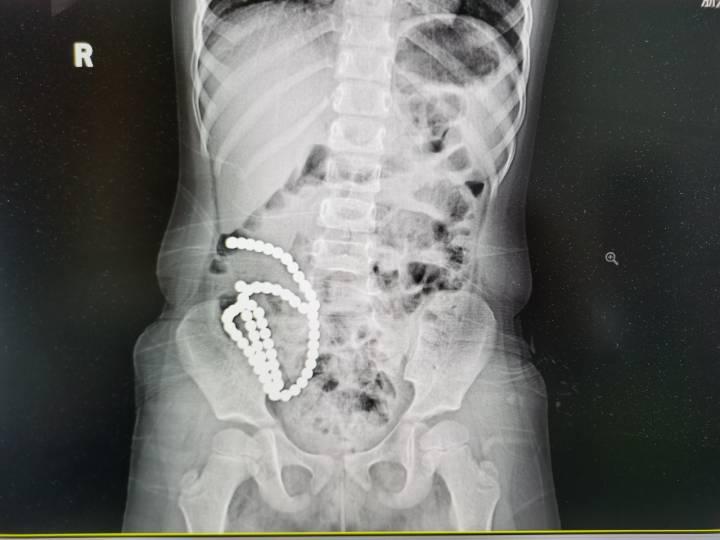

61颗磁力珠,14处肠穿孔,最近浙大儿院接诊了一例严重异物吞食的患儿,让经验丰富的医生都痛心疾首。

彤彤反复腹痛一个多月,一直以为是普通的肠胃炎,近来症状加剧到当地医院就诊,CT检查发现她肚子里有密密麻麻一长串珠子!医生建议赶紧转到上级医院治疗。

术后,医生统计了一下,他们共从患儿肠道内取出61颗磁力珠,这一连串珠子造成了14处肠穿孔。